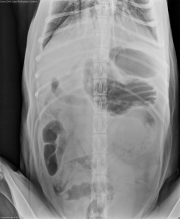

This week’s case is a 7-year-old male neutered Giant Schnauzer with abdominal discomfort and vomiting after being groomed. This case is a common presentation in the emergency room. What is your interpretation?

Abdomen: The stomach is mildly distended with gas. The fundus appears to be ventrally positioned on the lateral projection with rugal folds visible. The pylorus is dorsally positioned. On the ventrodorsal projection, both the fundus and pylorus are positioned on the left side of the abdomen. The duodenum appears to cross midline and join the pylorus on the left side. The spleen is malpositioned, with the proximal extremity not visible on the v/d, and the distal extremity and body in a curved shape in the ventral abdomen on the lateral projection. The remainder of the small intestine and colon appear normal.

Thorax: The cardiovascular structures are normal in size and shape. Megaesophagus is visible on multiple images. The left 5th and 6th costochondral junctions are prominent.

• Gastric dilation and volvulus with splenic torsion

• Secondary megaesophagus

• 180 degree gastric dilation and volvulus. Derotation and gastropexy were performed.